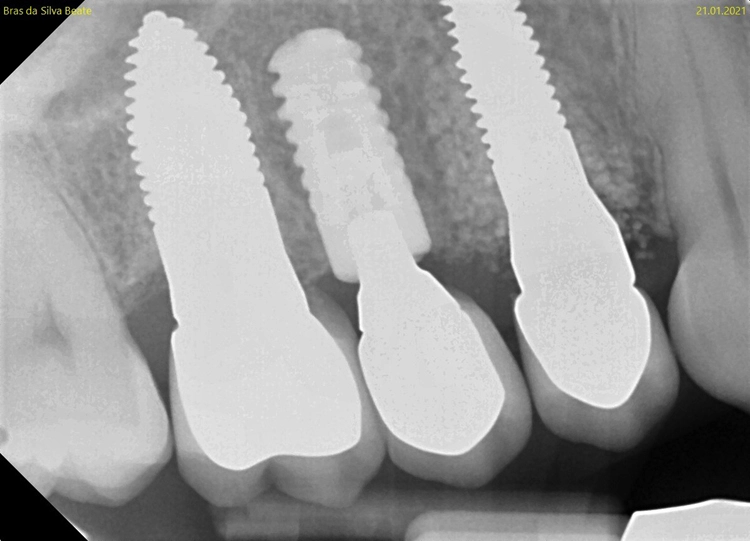

Nach der ersten klinischen Befundaufnahme und Fotodokumentation der Ausgangssituation (Abb. 1) wurde zur Ergänzung des klinischen Befundes eine Einzelzahnaufnahme erstellt (Abb. 2). Vom Oberkiefer wurde eine Abformung genommen, um eine Tiefziehschiene herzustellen. Diese wird direkt am OP-Tag genutzt, um eine provisorische Krone herzustellen.

Kontrollbild und Röntgenkontrolle ein Jahr und ein Monat nach Socket/Ridge Preservation (Abb. 21 und 22). Der komplette Umbau zu Eigenknochen ist noch nicht abgeschlossen. Die Papillenregeneration zwischen 13/14 und 14/15 ist jedoch deutlich erkennbar.